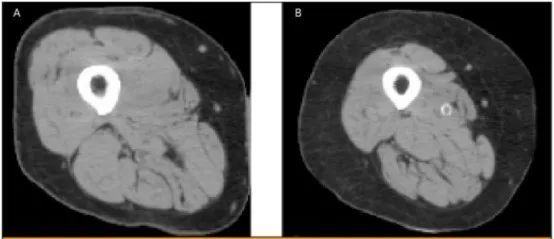

文章插图

同为72岁、BMI(身高-体重指数)= 25女性大腿肌肉的横断扫描 , 左图为正常 , 右图是肌少症患者 。